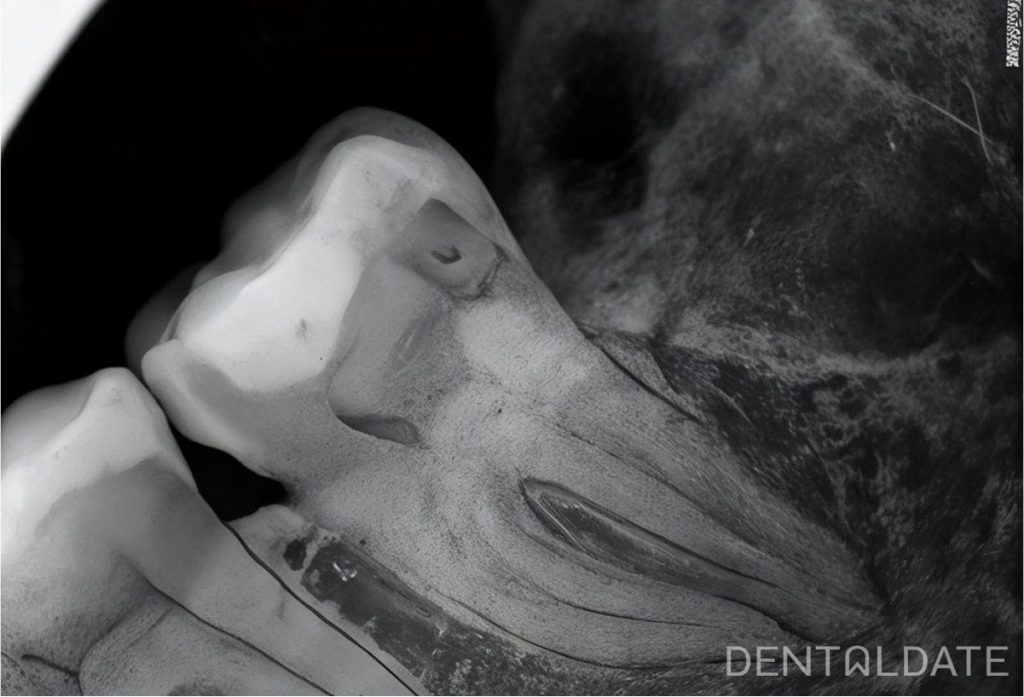

Under application, infiltration and mandibular anesthesia with Articaine 3.4 ml 1:00 000 solution, an incision was made in the retromolar region and cheekwise in the area of the 37th tooth, the mucosal periosteal flap was peeled off, the tooth was divided into parts (the distal part of the tooth crown was separated) using a boron machine, a corticotomy was performed cheekwise with a Lindeman milling cutter, the tooth was extracted using a straight luxator and forceps. The mandibular nerve is visualized in the root canal. Relaxing incision in the area of the connective tissue flap. Catgut sutures 5\0 #3. Amoxiclav 1000 mg 2 times a day for 7 days, loratadine 10 mg (1 tablet) 2 times a day for 3 days. Painkiller ibuprofen 100 mg 2 times a day for 3 days.